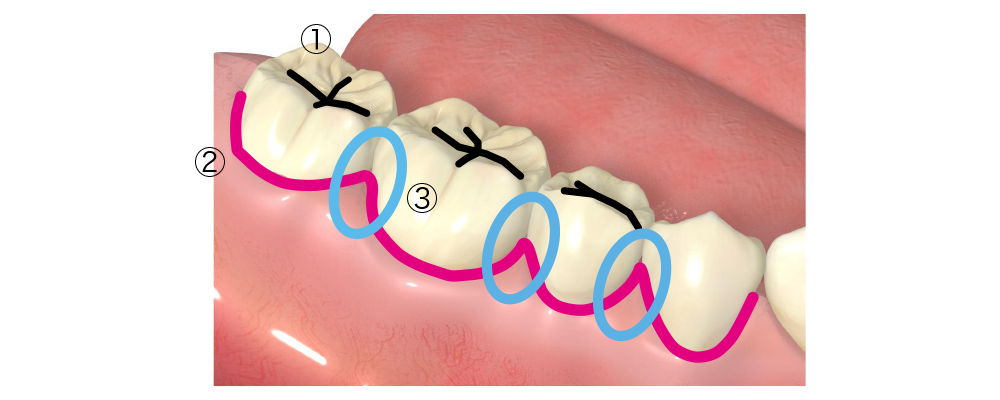

虫歯になりやすい場所

①奥歯の咬合面

奥歯は、食べ物をすりつぶす役割を担っているので咬む面が他の歯に比べ広い面積を持っています。そのため、溝が深く歯ブラシの毛先が届きにくいため、汚れが溜まりやすくくなります。

②歯と歯ぐきの境目

歯と歯ぐきとの境目には、約1~3mm程度の深さの溝が歯の全周にあります 。加齢や歯周病で歯ぐきが下がると露出する根元は、柔らかく酸に弱いため虫歯リスクが高い場所です。

③歯と歯の間(歯間部)

歯ブラシの毛先が届きにくく、磨き残しが生じやすくなります。デンタルフロスや歯間ブラシが必要な場所です。